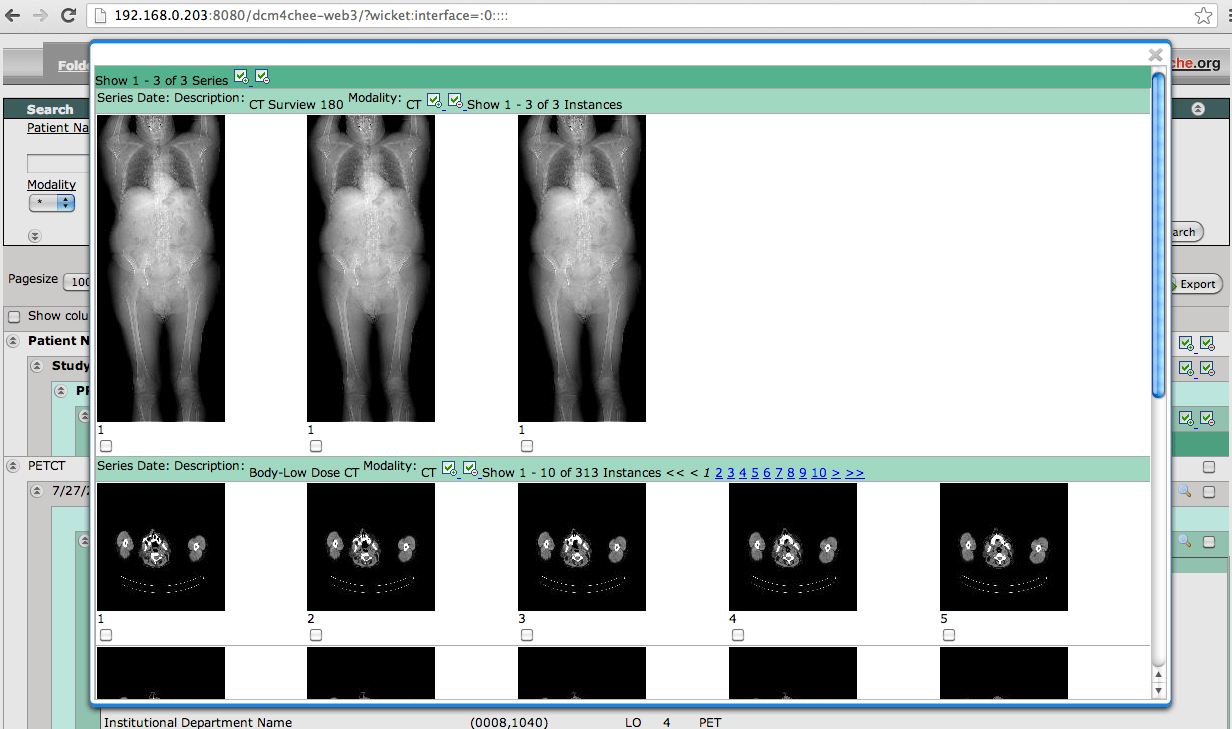

4. dcm4che

Unlike the other titles on this list, dcm4che is a Java-based suite of high-performance applications collected for the healthcare enterprise and it is used worldwide by researchers and in both open source and commercial applications.

dcm4che enables you to store any DICOM object type in standard file systems with full support for Client/Server PACS model, DICOM IOD’s, multiple platforms, and several IHE integration profiles.

Its features also include a web-based GUI for administrators, an integrated HL7 server which can act on ADT, ORU, and ORM message types among others.